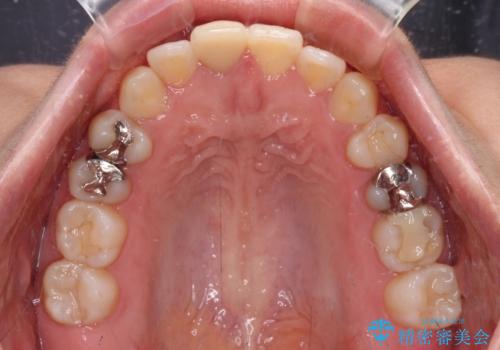

上顎歯列は歯の移動量が少なかったため、セラミッククラウンは装置を装着せずに治療を終えることができました。

- 学生時代に行った抜歯矯正の後戻りで、隙間ができてしまったことを気にして来院された患者様です。

マウスピース矯正を検討されていましたが、後戻りの隙間が非常に大きく、奥歯を前方に移動させる必要があるため、ワイヤー装置にて矯正治療を行うこととしました。